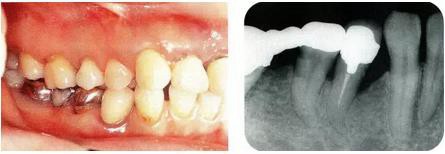

圖17-1 ( 左 ),2  ( 右 ) ▲  右下4近中9mm的骨緣下缺損,兩側(cè)全口橋體修復(fù),但是這顆患牙保留的情況下會(huì)影響牙列的維持,鄰接牙的骨水平在較高的位置,拔牙后可以獲得平坦的骨水平。即使是右下4嘗試再生療法,假說(shuō)可以100%的成功,右下3遠(yuǎn)中骨水平也會(huì)形成3mm以上的臺(tái)階。而且再生治療也需要患者登上1年半以上的時(shí)間。所以最終選擇拔牙的處理。